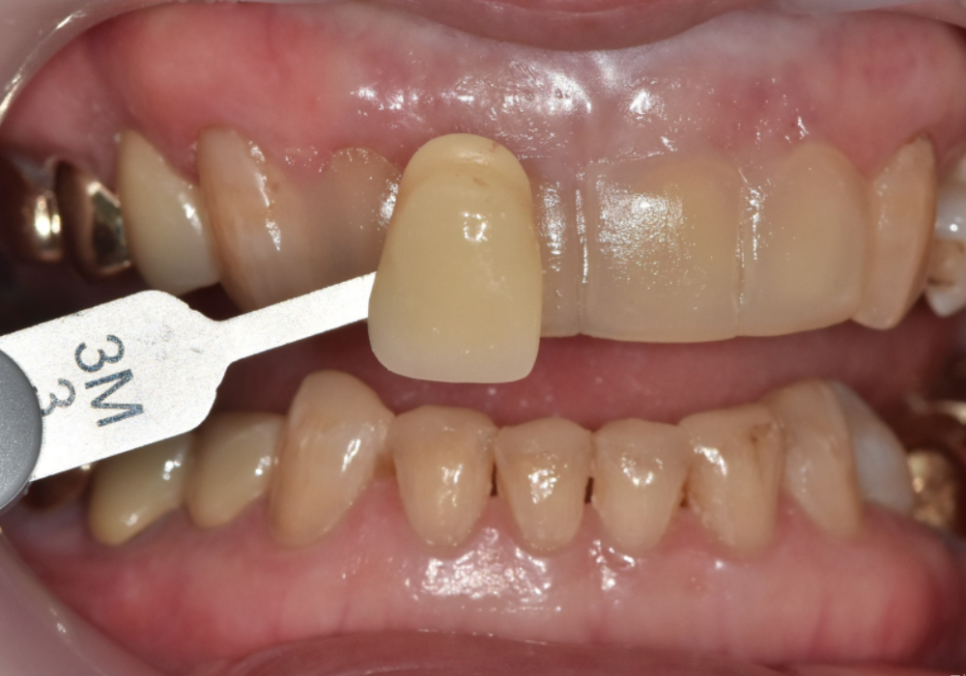

250304

저희 치과는 원내 기공실을 운영하고 있어

라미네이트 보철을 외부 기공소로 보내지 않고

병원 안에서 직접 제작하고 있습니다.

그래서 진료실에서 본 실제 치아 상태와

기공 과정이 자연스럽게 이어집니다.

치료하는 의사가

기공 과정 전반에 직접 참여하면서

라미네이트의 두께, 형태, 길이,

그리고 색감과 투명도까지

중장년 라미네이트, 70대도 가능한가요? 왜소치와 벌어진 앞니 해결 사례

환자분 얼굴과 기존 치아에 어울리도록

세밀하게 맞춰 갈 수 있습니다.

또 시적(끼워 보는 과정) 후

말할 때나 웃을 때 느낌을 바로 확인하고,

필요하면 그 자리에서 기공실과 상의해

조금 더 다듬어 드릴 수 있습니다.